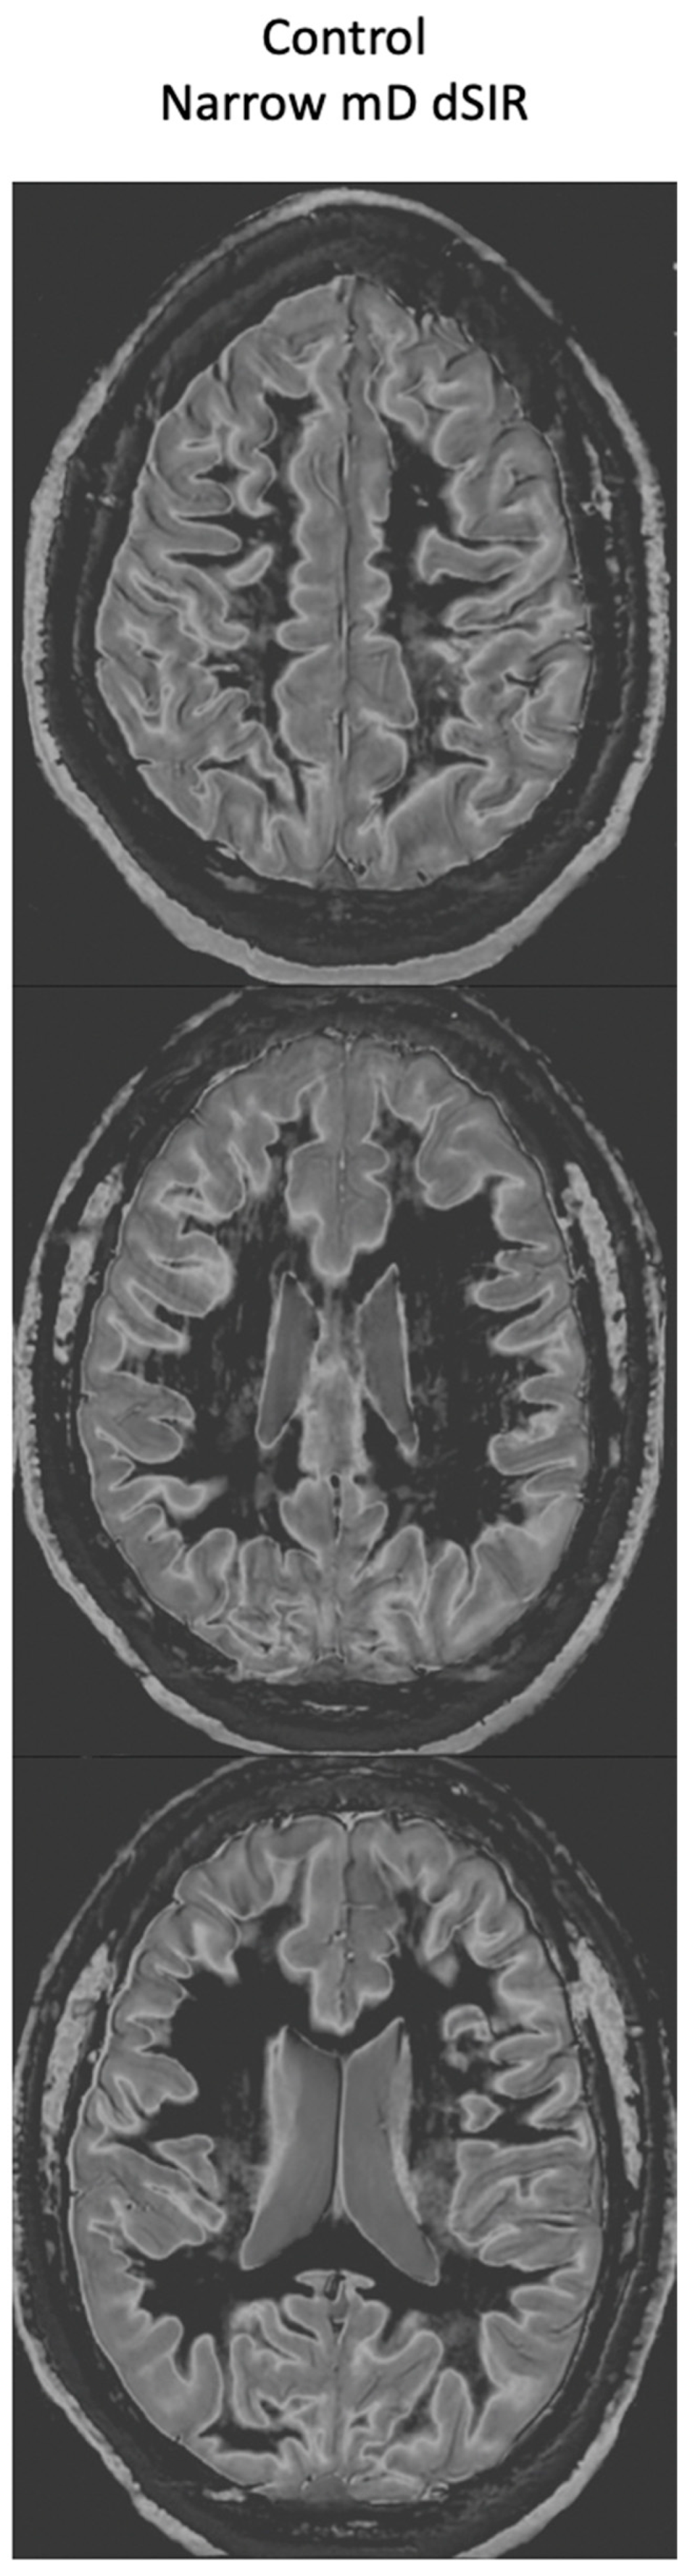

Figure 16.

Normal 18-year-old control. 2D narrow mD dSIR images. The narrow mD dSIR images show normal white matter as very low signal intensity (dark) except for intermediate areas in and around the corticospinal tracts. This is a whiteout sign grade 1. Normal high signal boundaries are seen at the junction between white matter and gray matter as well at the junction between white matter and CSF around the lateral ventricles.

Figure 16 shows narrow mD dSIR images from the normal 18-year-old control. His white matter is normal and shows a low signal (dark) appearance with a mid-gray appearance in and around the corticospinal tracts (whiteout sign grade 1, Table 2). Normal high signal boundaries (white lines) are seen at junctions between white and gray matter.